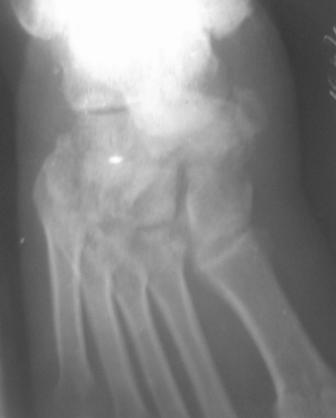

Re: Застарелый вывых ладьевидной кости стопы

По данному случаю, оказалось 3 месяца назад было произведена Р-графия в райбольнице, но больной предпочел лечится у табиба. Присылаю первичные снимки.